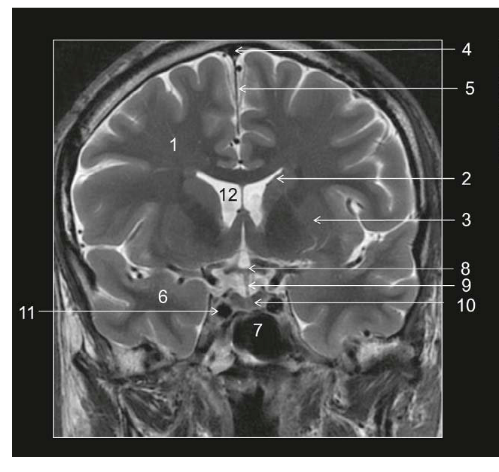

Coupe ? Légende ?